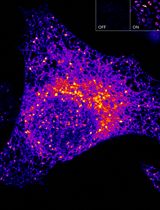

- Illustrated are data obtained in FRET assays that monitor [Ca2+]i using the YC3.60 reporter, the CCK2R agonist DG2, and cells that express the CCK2R (see legend for Figure 3).

Figure 3. Dose-dependent action of demogastrin-2 (DG2) at the human CCK2 receptor to increase [Ca2+]i as detected using YC3.60. A. Raw data obtained from a single well on the reading plate illustrates the time-dependent reciprocal decrease and increase of 485 and 535 nm YC3.60 relative fluorescence unit (RFU) emission intensity in response to application of CCK2 receptor agonist DG2 (300 nM) to suspensions of HEK293-hCCK2R c29 cells adenovirally transduced with YC3.60. B. Determination of the single well percent change of YC3.60 535/485 nm emission ratio (% ∆FRET) calculated using the single well raw data illustrated in panel 3A. An increase of the 535/485 nm FRET ratio signifies an increase of [Ca2+]i. C. DG2 produced a time-dependent and dose-dependent increase of the 535/485 nm YC3.60 FRET ratio. Data for each time point is the mean % ∆FRET ± S.D. for n = 6 wells. D. Non-linear regression analysis of the data illustrated in panel 3C demonstrated that the EC50 for DG2 action in this cell line was 604 pM. Non-linear regression analysis was performed with Origin 8 software using the highest ∆FRET values for each data point. Non-linear reduction can also be performed with GraphPad Prism 8. For instruction in how to obtain values for time-dependent, dose-dependent and non-linear reduction with SoftMax Pro 7.1 see Video 2.